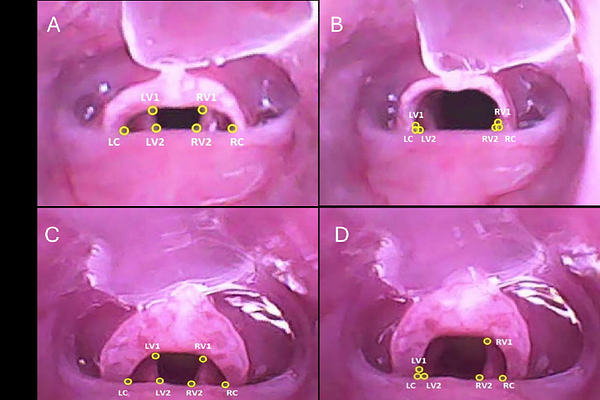

Vocal fold mobility is essential for normal laryngeal function and is often compromised following recurrent laryngeal nerve (RLN) or superior laryngeal nerve injuries. In a rat model of unilateral (RLN) injury, we quantitatively evaluate laryngeal mobility using advanced computer vision techniques. Adult male Long-Evans rats underwent direct laryngoscopy before and after RLN injury at the level of the 5th tracheal ring. High-resolution video recordings were analyzed with the open-source deep learning framework Social LEAP Estimates Animal Poses (SLEAP) to track key laryngeal landmarks. The displacement of the left and right arytenoid processes relative to the anatomical midpoint was measured frame-by-frame. Mean differences and 95% CI were computed for each arytenoid. A mean difference threshold of 0.42 differentiated laryngeal asymmetry from symmetry. This method offers a quantitative method of assessing laryngeal symmetry in a rat model.